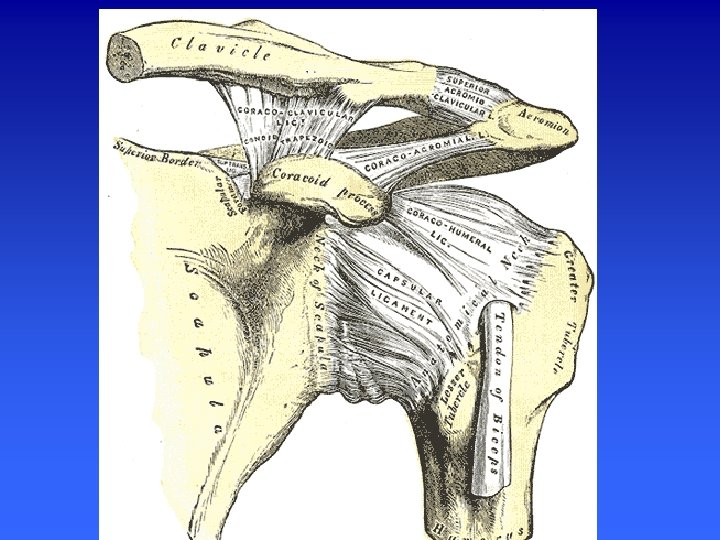

STRUCTURES OSSEUSES de l’épaule n FACE ANTERIEURE : n n n Clavicule Corps de l’omoplate, fosse scapulaire Apophyse coracoide Acromion Glène Tete de l’humérus n FACE POSTERIEURE n n Corps de l’omoplate Épine de l’omoplate Tete humérale Acromion

Éléments de la stabilité active La coiffe des rotateurs • • Supra-épineux Infra-épineux Petit rond Subscapulaire Le tendon du long biceps

SOUS SCAPULAIRE Insertions : fosse sous-scapulaire de l'omoplate. insertion sur la partie haute du trochin. Actions : un rotateur interne et un adducteur pour l'humérus il fait partie des moyens de stabilisation antérieure de l'articulation gléno-humérale. Il est un stabilisateur de la longue portion du biceps au sein de sa gouttiére il s'oppose à l'excentration vers le haut de la tête humérale lors de la mise en tension du muscle deltoïde TM

SOUS EPINEUX (M. Infraspinatus) Aplati et triangulaire Insertions : le corps musculaire s'insére sur les 3/4 internes de la fosse sous épineuse par implantation directe de fibres charnues et des lames aponévrotiques attachées sur les crêtes osseuses le corps charnu, se dirige en dehors et vient s'insérer sur la facette antéromoyenne du trochiter Action : Rotateur externe du bras, abducteur du bras

SUS EPINEUX (M. Supraspinatus) Epais et triangulaire Insertions : 2/3 internes de la fosse sus épineuse se dirige en dehors s'inséree sur la facette antérosupérieure du trochiter. Action : Rotateur externe du bras, abducteur du bras (éléve le bras à angle droit, comme le faisceau moyen du deltoïde

MUSCLE PETIT ROND (M. Teres Minor) Muscle aplati et allongé, situé sous le sous épineux. Origine : A la face postérieure de l’omoplate, le long de son bord externe Insertion : sur le trochiter et sur le bord externe de l’humérus. Action : Rotateur externe de l’épaule.

1. le long biceps naît au-dessus de la cavité glénoïde de l’omoplate par un tendon qui traverse d’abord la capsule , se coude, passe entre le trochiter et dans la coulisse bicipitale. De ce tendon naissent des fibres charnues qui rencontrent celles du court biceps. 2. le court biceps naît par un tendon sur l’apophyse coracoïde puis devient charnu et rejoint le long biceps